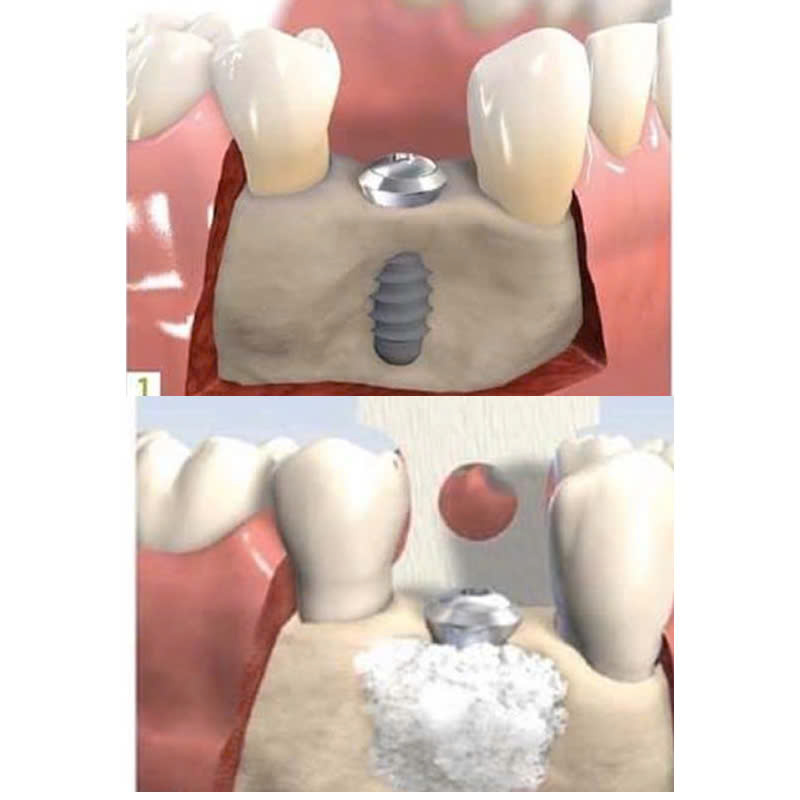

Quy trình ghép xương nhân tạo thường được thực hiện trong 2 giai đoạn chính:

Giai đoạn 2: Tiến hành phẫu thuật ghép xương

- Bác sĩ sẽ tiến hành phẫu thuật lộ khu vực xương cần ghép, sau đó đặt các vật liệu xương nhân tạo vào vị trí cần tạo khối lượng xương.

- Vật liệu ghép xương sẽ được bác sĩ cố định tại chỗ bằng keo hoặc vít, tuỳ theo từng loại vật liệu ghép.

- Vùng ghép xương sẽ được khâu lại cẩn thận để đảm bảo hồi phục tốt.

Thời gian chờ đợi để vật liệu ghép xương tích hợp với xương tự nhiên thường mất khoảng 3-6 tháng trước khi có thể tiến hành trồng răng implant.